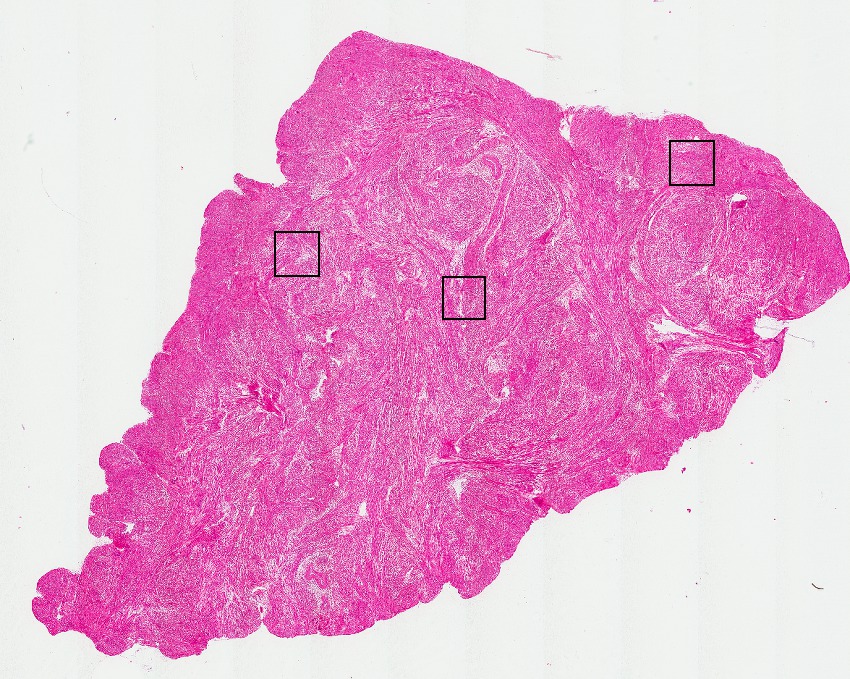

Smooth muscle cells:

95

Other cell types:

5